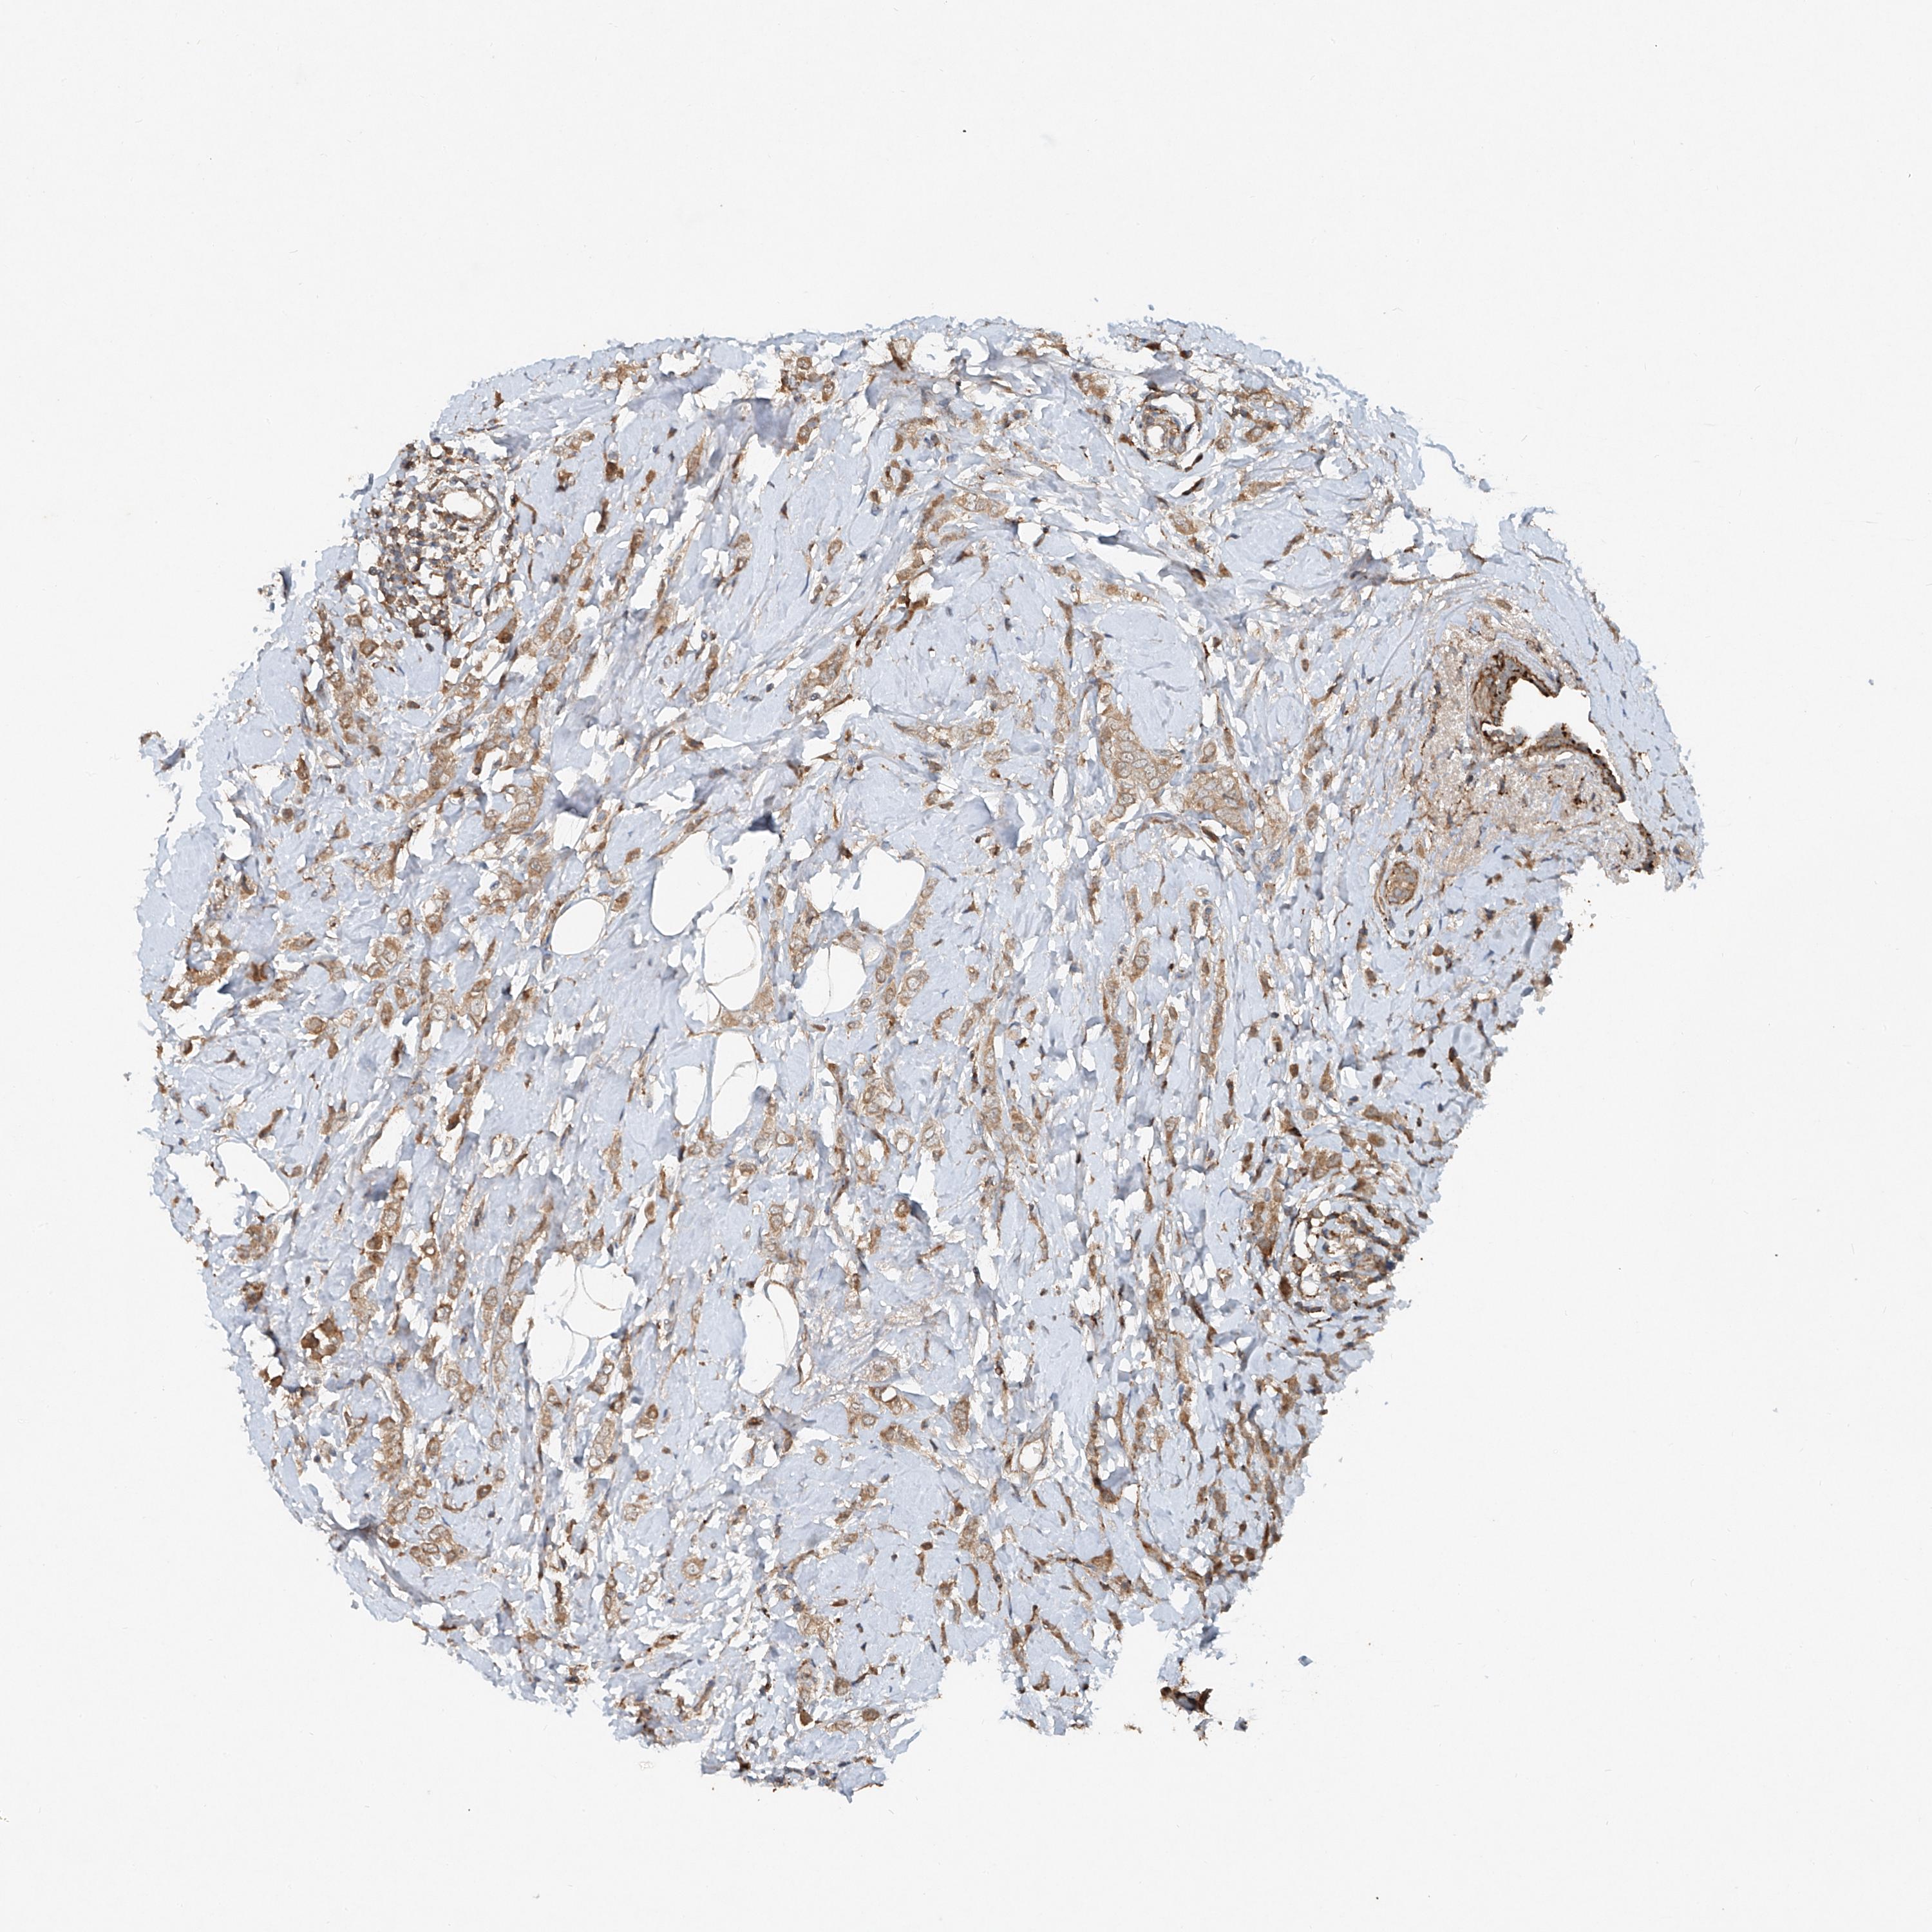

BRCA TCGA BRCA VALIDATION PROTEIN EXPRESSION

Breast cancer

Human cancer